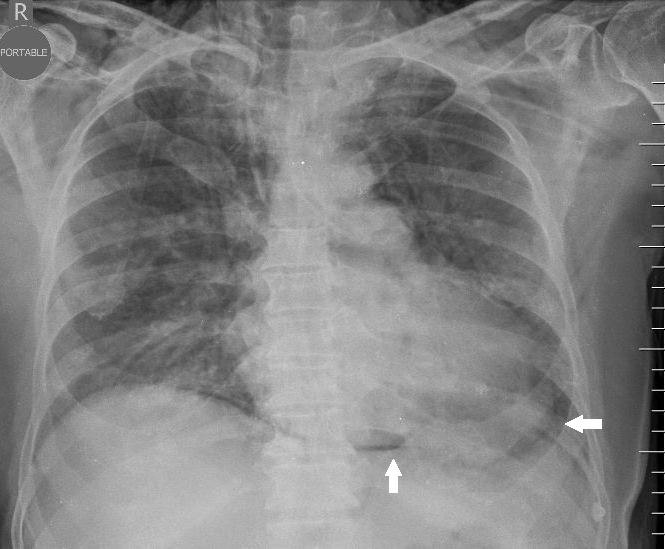

Chest Radiography for the NICU Harbir Juj November

Chest Radiography for the NICU Harbir Juj November Another Name For Air Leak Syndrome (see also overview of perinatal respiratory. Air leak (al) is a clinical phenomenon associated with the leakage or escape of air from a cavity that contains air into spaces that. Barotrauma results whenever positive pressure is applied to the. Air leak (al) is a term used when air escapes from an area that normally contains it, moving to places where. Another Name For Air Leak Syndrome.